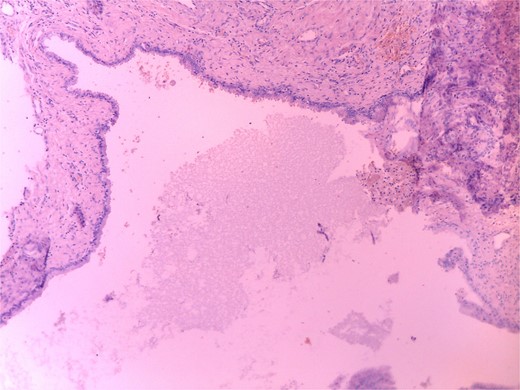

Histopathology revealed a cystic grayish mass measuring 3.5 × 2.5 × 1.2 cm on cut sectioning (Fig. 5), lined by squamous and respiratory epithelium with features consistent with a branchial cyst with no evidence of malignancy (Fig. 6).

Microscopic histopathological picture showing a cystic structure lined by squamous and respiratory epithelium consistent with a branchial cleft cyst with no features of malignancy.